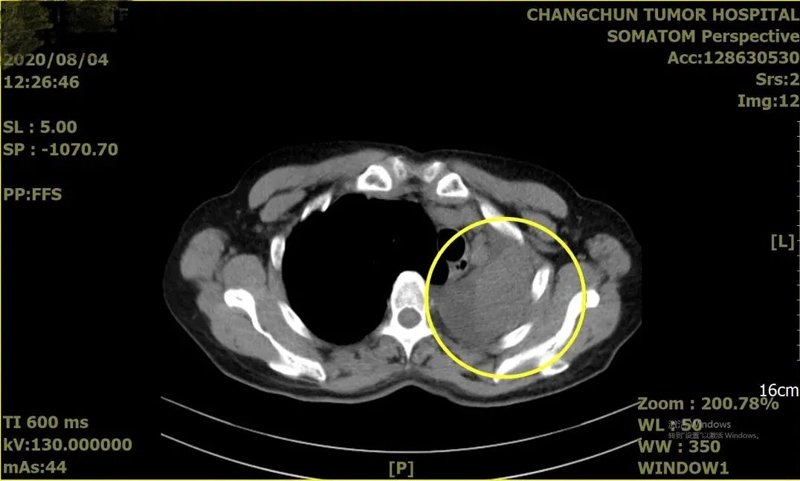

张女士是个老烟枪,近一年一直反复出现咳嗽、咳痰、呼吸困难。每次严重一些就到当地诊所打抗炎药,症状有所缓解就没有进一步检查,今年2月份,症状加重的她在家人的陪同下鼓起勇气来到长春就诊。经过肺部CT检查,竟然发现左肺占位——这意味着极可能得了肺癌。

就在走投无路的时候,患者及家属来到长春肿瘤医院,胸外科根据患者的初步诊断,迅速组织介入科、呼吸内科、影像科、麻醉科进行MDT多学科会诊,会诊后由气管镜专家徐伟主任为张女士制定了针对性的气管镜方案,在保障患者安全的情况下进行了支气管检查,检查发现:气管隆突锐利,左主气管中段可见新生物,堵塞管腔;后经病理科主任杨华回报结果显示为:浸润性鳞状细胞癌。手术已刻不容缓!